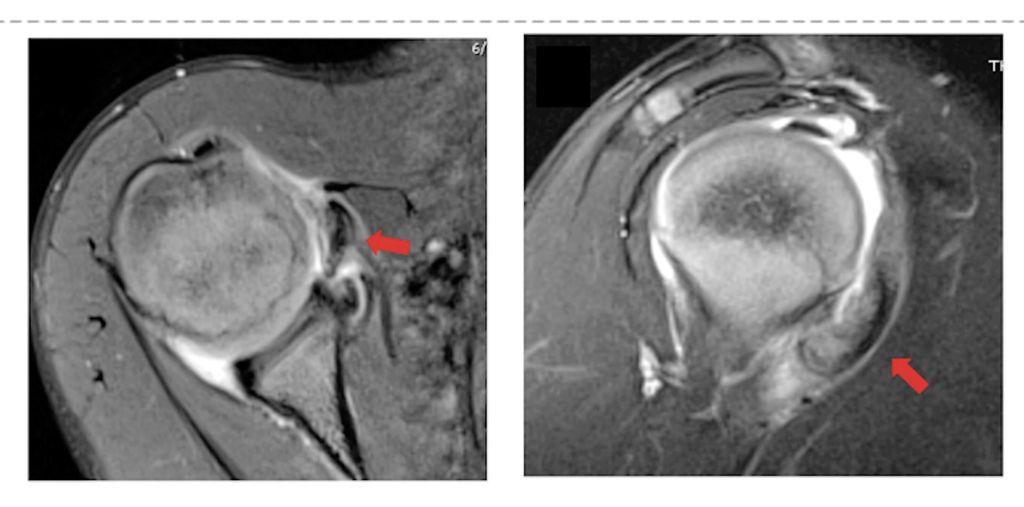

Das Hauptproblem ist die Tatsache, dass Instabilität eine funktionelle Problematik und nicht automatisch mit strukturellen Veränderungen assoziiert ist. Auf der anderen Seite können auch strukturelle Veränderungen auftreten, ohne dass eine Instabilität entsteht oder entstanden ist. So kann zum Beispiel die überweite Kapsel als kausale Pathologie für die multidirektionale Schulterinstabilität (MDI) am nativen MRI nicht beurteilt werden (Gefahr falsch negativ). Auf der anderen Seite können zum Beispiel die Wachstumskerne am anteroinferioren Glenoid, die regelmässig bis spät in die zweite Dekade nicht fusionieren, als ossäre Bankert-Läsion fehlgedeutet werden (Gefahr falsch positiv) (Abb. 1).

Abb. 1: Der anteroinferiore Knochenkern des Glenoids fusioniert erst in der 2. Dekade und kann mit einer Bankart-Läsion verwechselt werden. Nach Sidhartan et al., Arthroscopy 2020